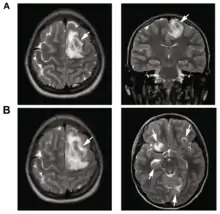

B: T1-weighted MRI showing expansion and addition of necrotic areas 4 days later